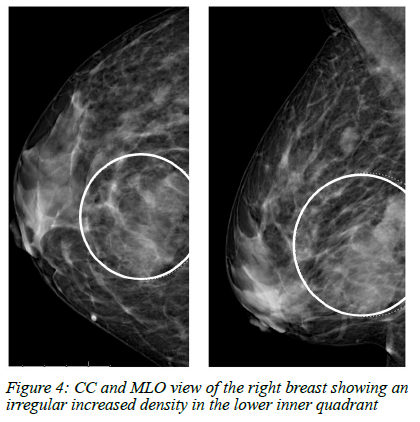

Mammogram